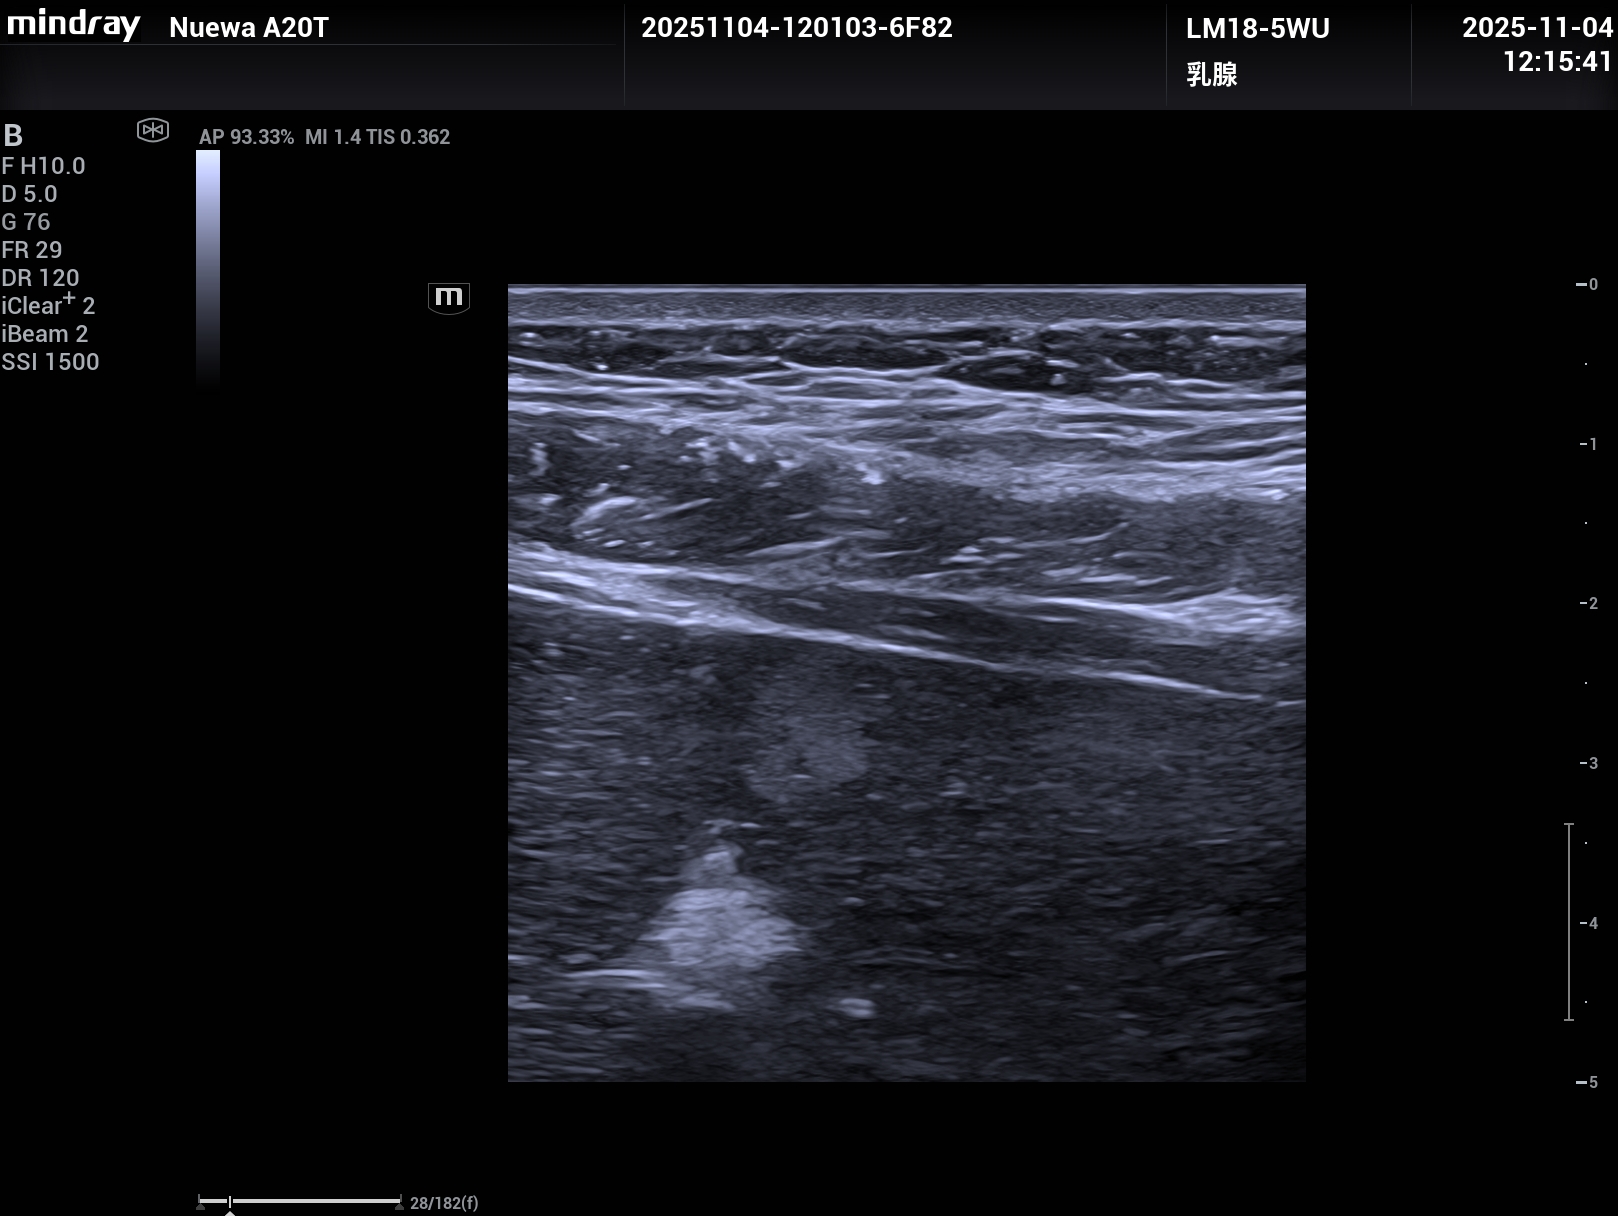

睿瞳技术,是具有独立的发射和接收电路设计的成像技术,组织回声信息更多,图像信息更丰富。

上2幅图是采用了Nuewa A20睿瞳技术的图片,下2幅是没有采用睿瞳技术的图片。